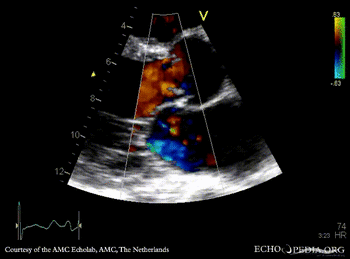

Severe aortic regurgitation

A5CH: Color Doppler signal of severe aortic regurgitation Continuous-wave Doppler signal of severe aortic regurgitation, PHT 135 msec